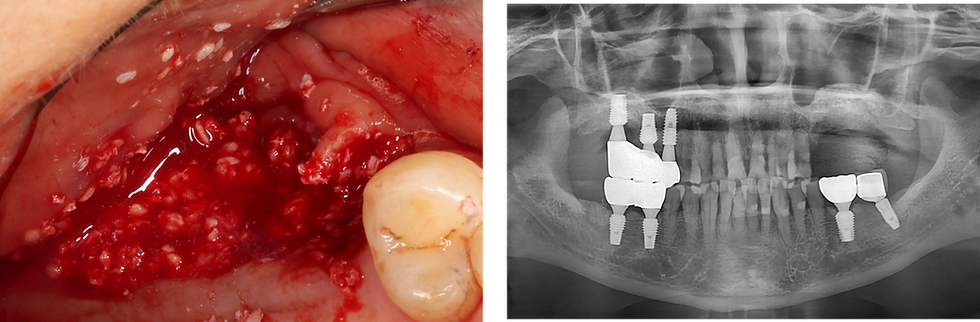

1ļøā£ Pre-Op

Intraoral photograph and panoramic radiograph taken on the first visit showing severe peri-implant bone loss around the #25-27, with the fixture threads exposed. Replacement with new fixtures was planned after removal of the existing failing fixtures

Bone graft materials was placed to restore the alveolar ridge and promote regeneration before re-implantation

The significant bone defect is clearly visible in the panoramic radiograph